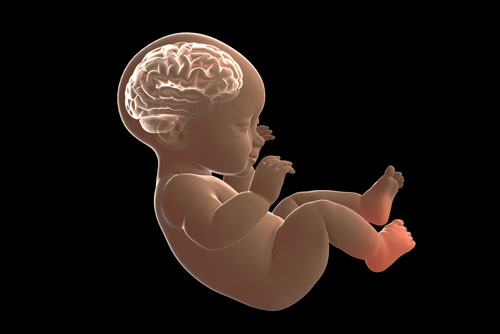

7- Bebekte Kafa ve Beyin Anomalileri

Anne karnında bulunan bebekte görülen kafa ve beyin anomalileri, en rastlanan ve ultrasonografik olarak erken tanı konulabilen anomaliler arasında yer almaktadır. Bebeğin kafatasının gelişmemesi, beyin dokusunun içindeki ayrıntılarda eksikler olması, beyin dokusunun açıkta kalması, sıvı dolu keseciklerin aşırı genişlemesi ve beyin dokusunun gelişmemesi en sık tespit edilen problemlerden birkaçı olarak öne çıkmaktadır.  Bu anomalilerin önemli bir kısmı hayatla bağdaşmamasından dolayı, bebek doğumdan kısa bir süre sonra kaybediliyor. Bu durumla karşılaşılan bebeğin hastalığın akıbetine ve ağırlığına göre, ailenin tercihleri yönünde, meslek ilke ve etiği çerçevesinde bir yol seçiliyor.